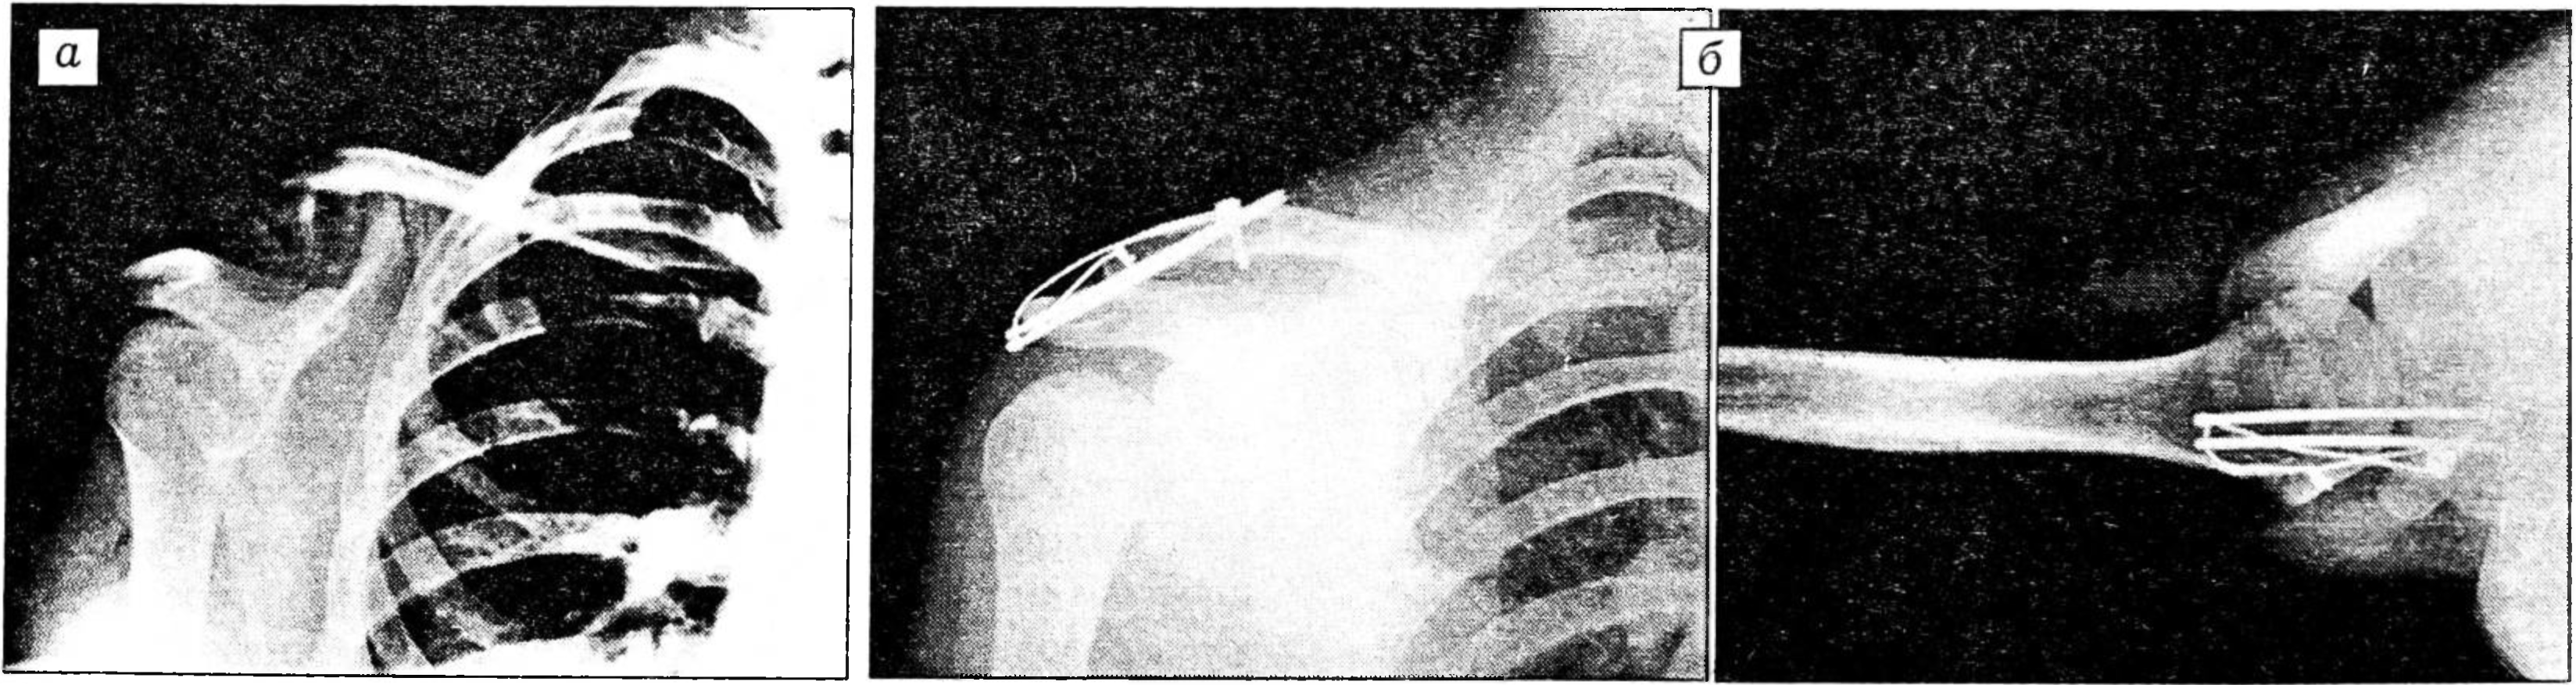

Послеоперационные осложнения при обычном варианте остеосинтеза спицами Киршнера и стягивающей петлей состоят в миграции спиц, их переломе, соскальзывании или обрыве серкляжной проволоки [4, 5, 7, 8, 14, 15]. При трансартикулярной фиксации акромиально-ключичного и грудиноключичного сочленений продолжительные по времени движения могут привести к усталостному перелому конструкции [7]. Поскольку мы применяли спицы диаметром 2 мм и обычно удаляли имплантат в ранние сроки, у наших больных таких осложнений не было (рис. 3). Однако при остеосинтезе грудиноключичного сочленения, учитывая сильное рычаговое действие плеча, следует дополнительно применять иммобилизацию повязкой Дезо [7].

Рис. 3. Больная 17 лет. Диагноз: перелом акромиального конца ключицы.

а — до операции; б — после остеосинтеза стягивающей петлей в модификации авторов.